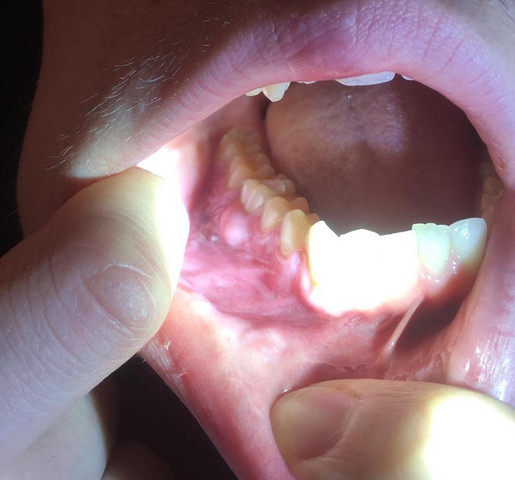

Entzündetes Zahnfleisch am Backenzahn Eine Entzündung des Zahnfleisches tritt sehr häufig durch eine mangelhafte Zahnhygiene auf. Unsere Dienstleistungen im Bereich Zahnimplantate. Das Programm zum weltweiten Versand USA und das Programm zum weltweiten Versand UK im weiteren Verlauf zusammen als das GSP bezeichnet machen bestimmte Artikel GSP-Artikel aus den USA und dem Vereinigten Königreich für Käufer auf der ganzen Welt verfügbar.

Hilfe Komische Blase Hinter Backenzahn Zahnmedizin Med1